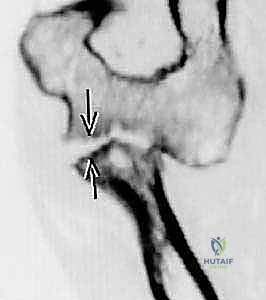

- الأشعة السينية (X-rays): يتم أخذ صور بأوضاع مختلفة (أمامي خلفي، جانبي، ومائل) لرؤية الكسر بوضوح. أحياناً يكون الكسر دقيقاً جداً ولا يظهر إلا من خلال علامة "وسادة الدهون المرفوعة" (Positive Fat Pad Sign) التي تشير إلى وجود نزيف داخل المفصل.

- الأشعة المقطعية (CT Scan): في حالات الكسور المفتتة أو المعقدة، يطلب الدكتور هطيف إجراء أشعة مقطعية ثلاثية الأبعاد (3D CT) لبناء تصور هندسي دقيق للكسر، مما يساعده في تخطيط العملية الجراحية واختيار الشرائح والمسامير المناسبة قبل دخول غرفة العمليات.